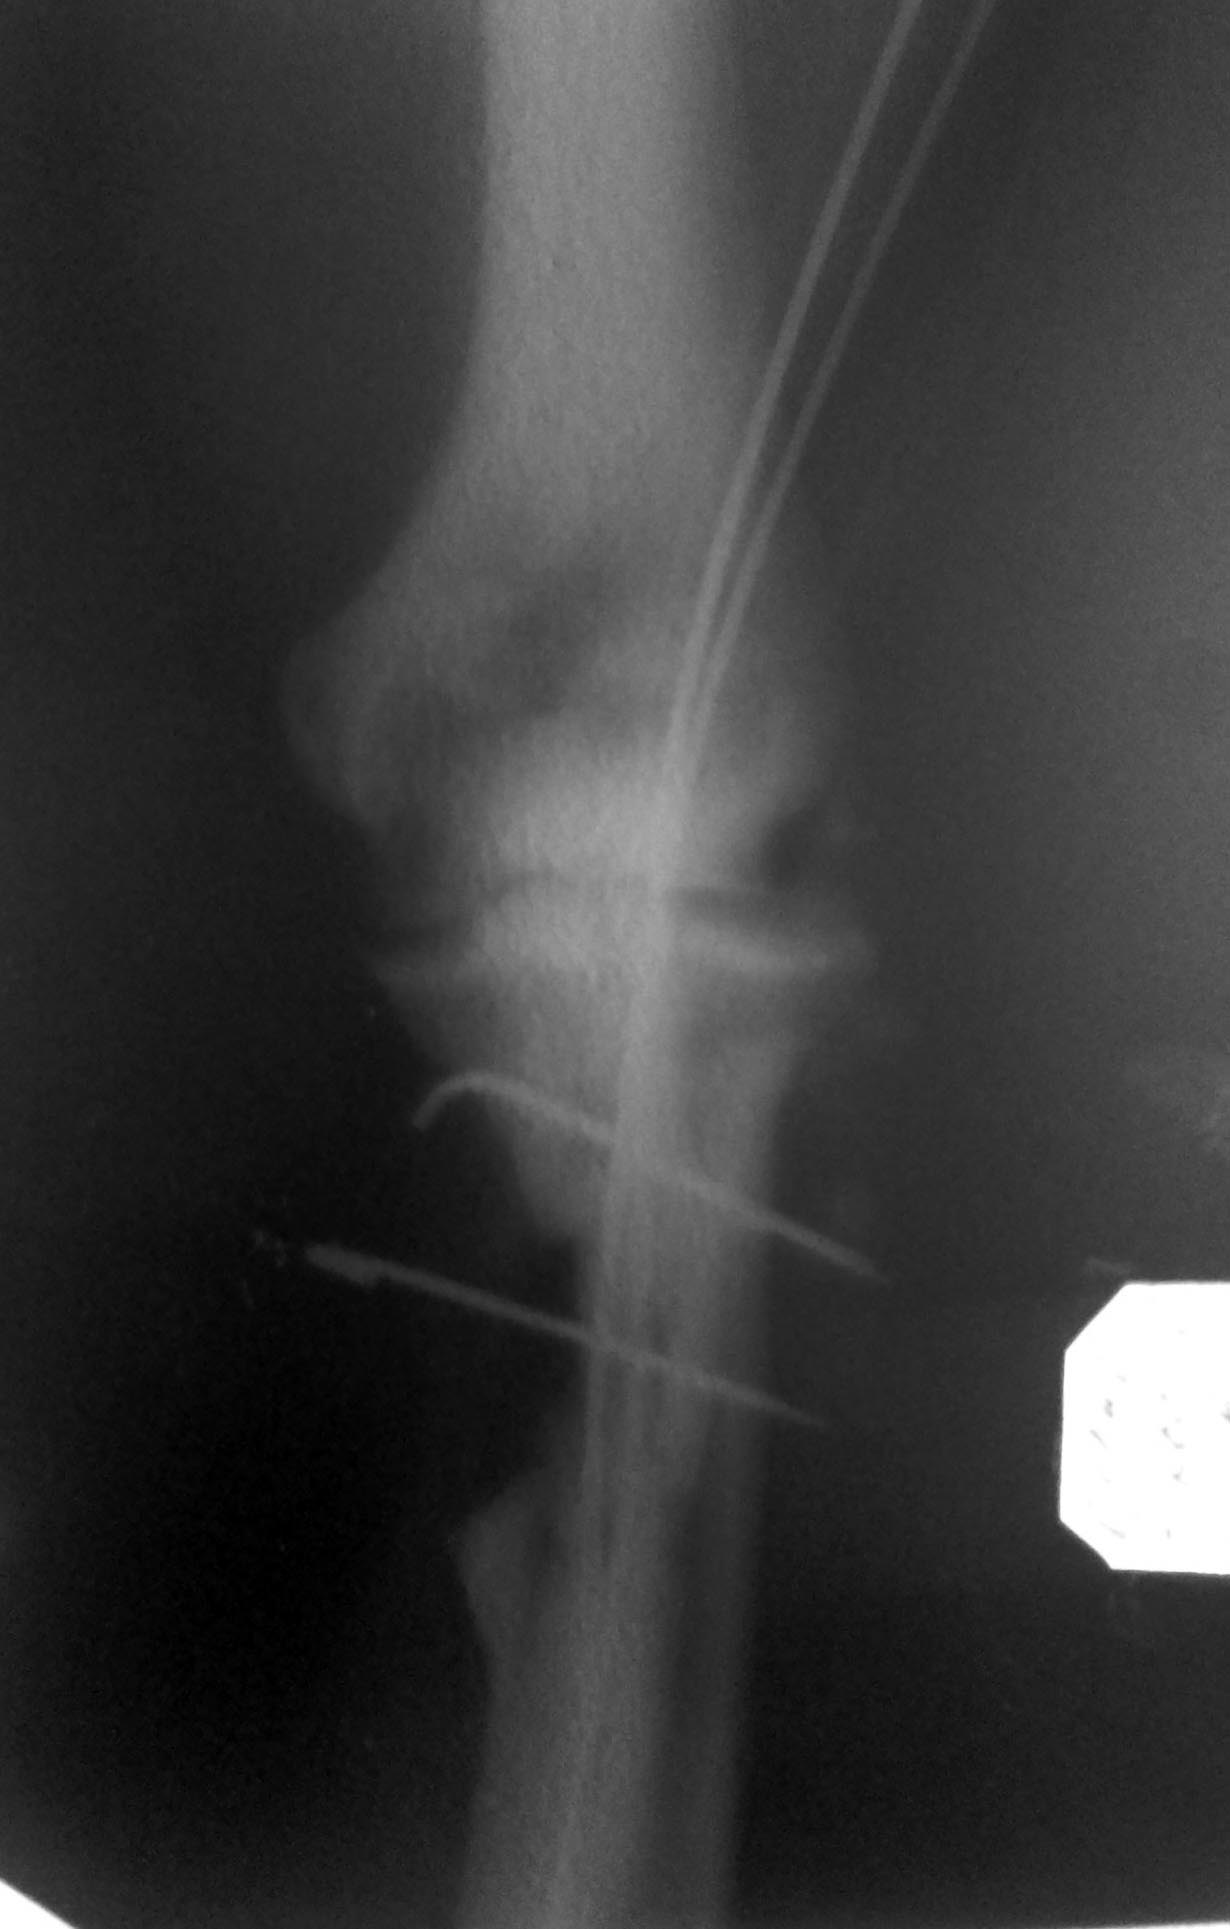

Вложение не в текстовом формате было извлечено…

Имя     : IMG690.jpg

Тип     : image/jpeg

Размер  : 135987 байтов

Описание: отсутствует

Url     : http://weborto.net:8080/pipermail/ortho/attachments/20130819/c355101e/attachment-0005.jpg